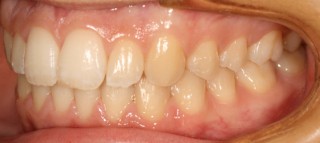

Um die Behandlung zu dokumentieren und für die Beratung der Patienten fertigen wir routinemäßig vor, nach und manchmal auf während der Behandlung Fotos von den Zähnen an.

Intraorales Bild02 [320x200] Intraorales Bild03 [320x200]